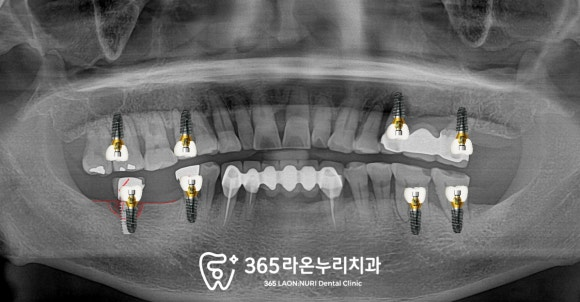

파노라마 엑스레이를 찍어보았는데요,

보이는 것처럼 이가 없는 곳은

텅 비어있는 게 보이고

치조골의 높이도 낮아진 부위가 있습니다.

■ 5. 최종 보철물 제작 및 체결

치료가 마무리된 모습을 보겠습니다.

픽스처 식립 개수는 최소로 하면서

구치부 기능은 모두 회복되었습니다.

최근에 정기검진을 오셔서

엑스레이를 찍어 살펴보니

관리도 잘되고 있으셨습니다.